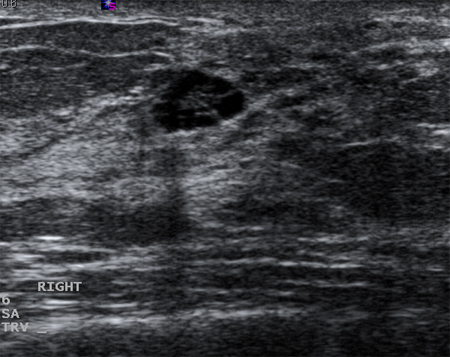

Imagen en ultrasonografía de un quiste complejo

Cortesía del Dr. Lane Roland, University of Louisville; utilizada con autorización

Ver esta imagen en el contexto de la/s siguiente/s sección/es:

Evaluación de masas en la mama